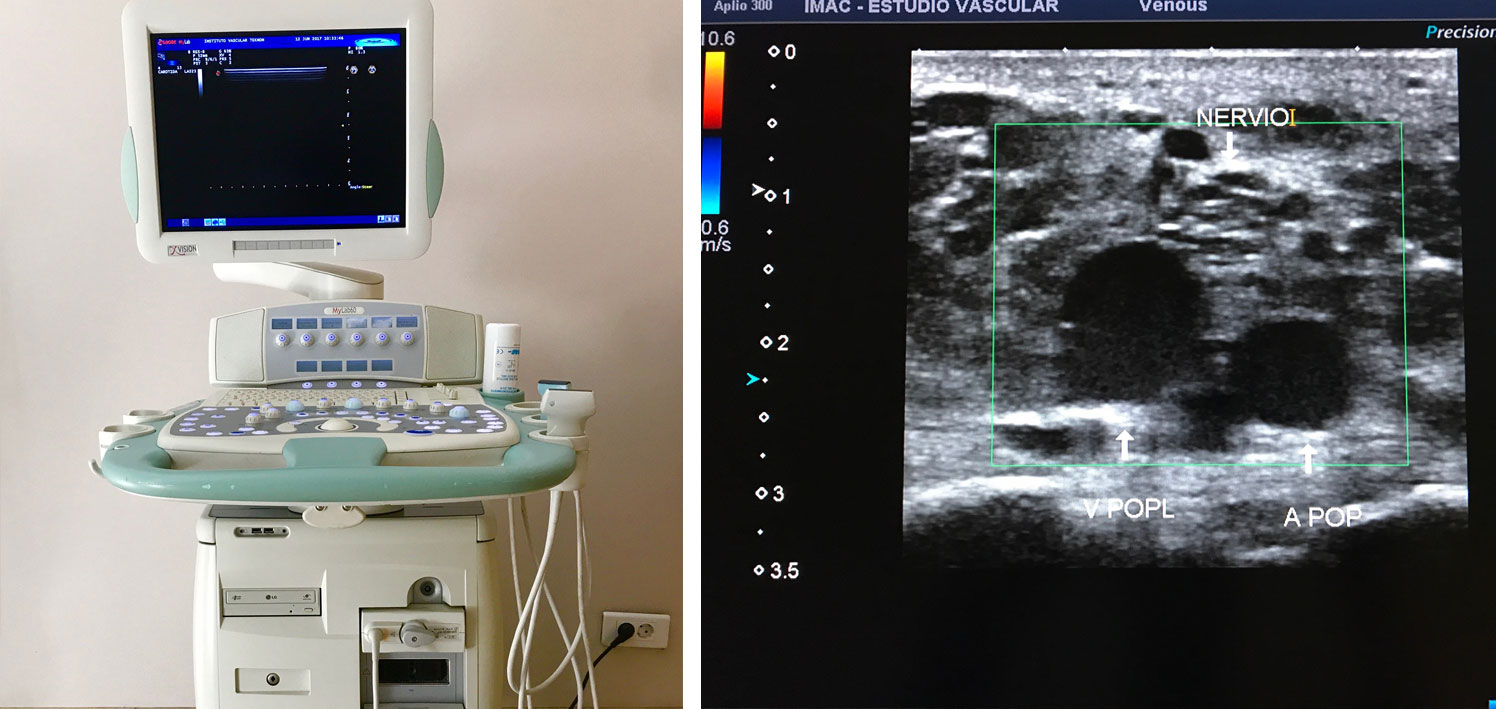

Ecografia Doppler Carotídea

< Volver a "Pruebas diagnósticas"La enfermedad aterosclerótica es la principal causa de morbi-mortalidad en pacientes con enfermedades inflamatorias sistémicas. Las arterias coronarias, aorta y carótidas son sitios muy susceptibles de afectación por placas ateroscleróticas. La ultrasonografía o ecografía carotÍdea permite la detección signos precoces y la toma oportuna de medidas correctivas para evitar la evolución. Los hallazgos en la ecografía carotidea en conjunto con otros territorios permiten estimar el riesgo cardiovascular con intención de personalizar cada tratamiento y evitar complicaciones.